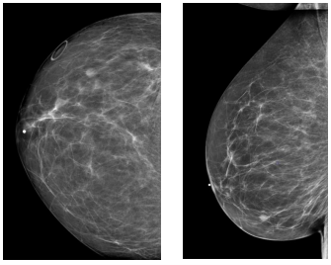

types of circumscribed IDC

papillary, medullary mucinous

papillary, medullary, mucinous